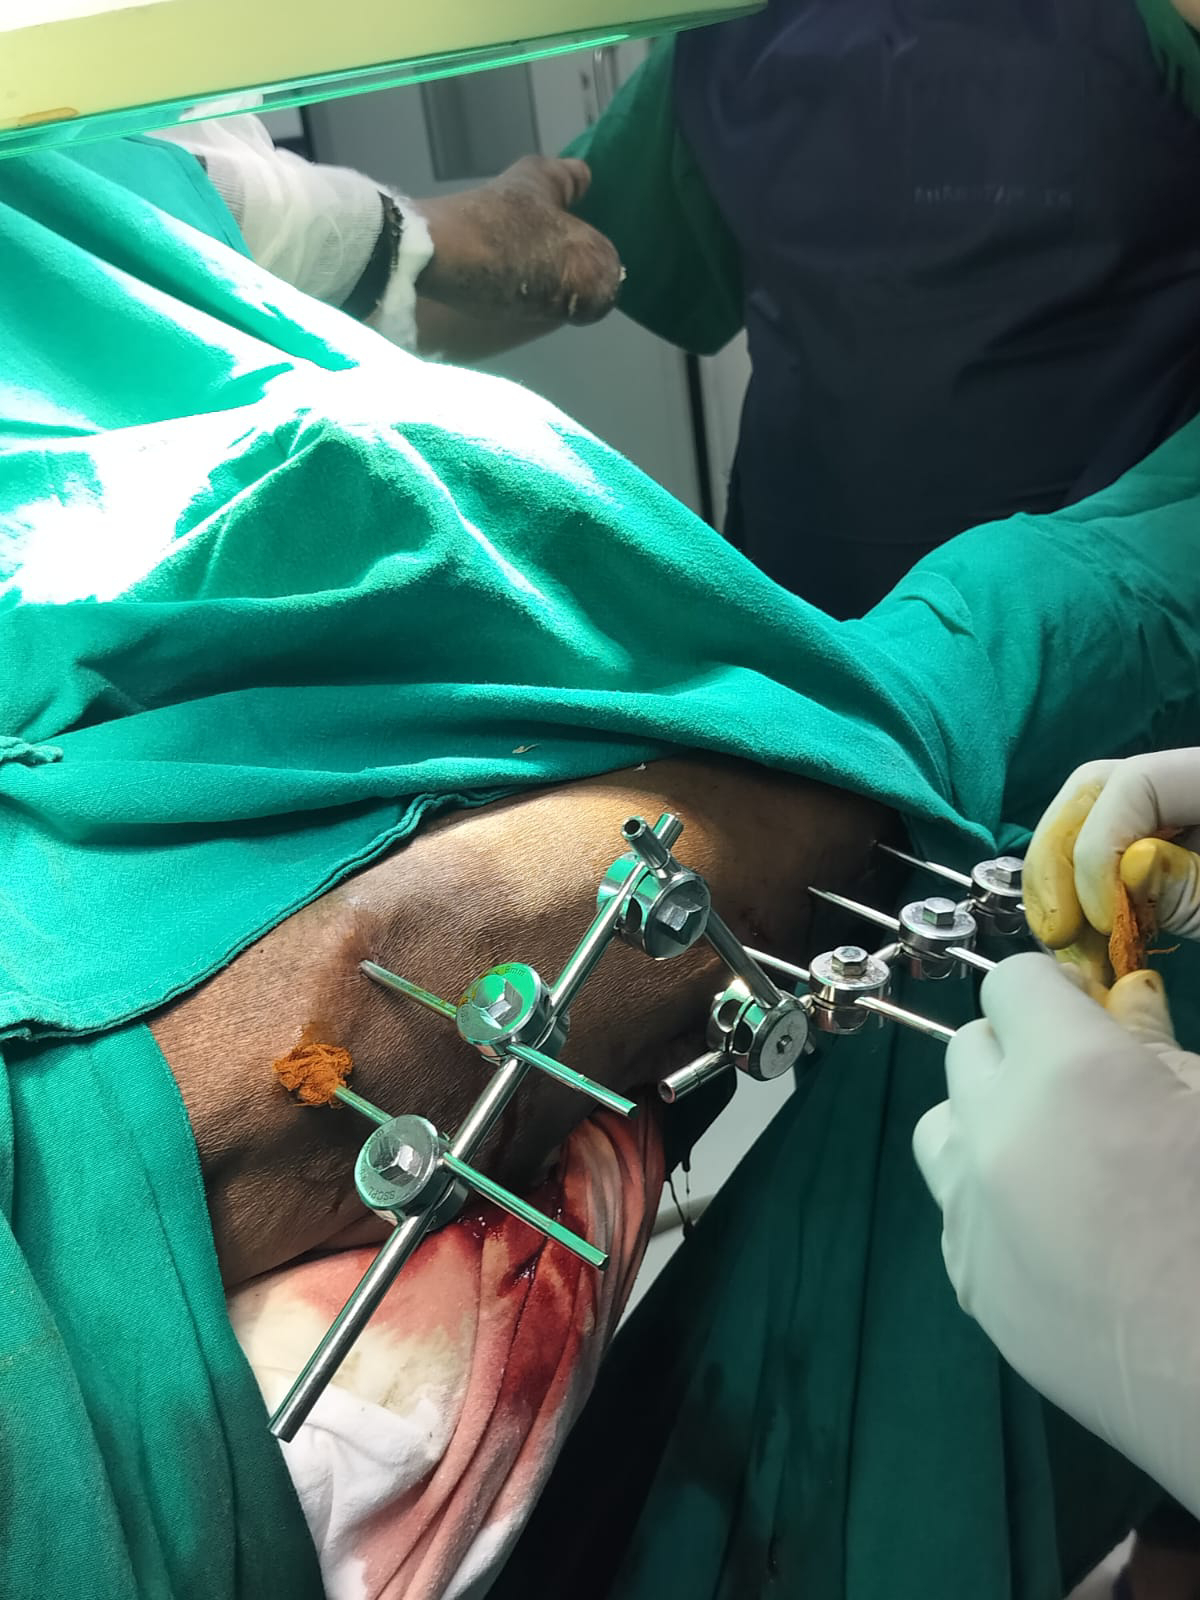

[8/27, 8:05 AM] pajr_member: Yes sir they have planned for external fixation under local anesthesia sir

[8/27, 8:37 AM] PaJR PHR Moderator: When today? Please share their notes ASAP

[8/27, 8:38 AM] +pajr_member: They said to shift case at 12:30pm sir

[8/27, 8:45 AM] PaJR PHR Moderator: Share their pre op plan as in what do they plan to do. What kind of external fixator are they planning

[8/27, 8:58 AM] PaJR PHR Moderator: Even if they are doing it in local as it's being done in OT the Anesthesiologist will be on standby

[8/27, 2:54 PM] PaJR PHR Moderator: Thanks @~pajr_member

Please ask them in how many days can we start mobilizing him

[8/27, 2:55 PM] +pajr_member: They said from today evening itself can start mobilizing him sir

[8/27, 4:15 PM] PaJR PHR Moderator: Fluoroscopic picture showing the placement of the uppermost pin in his fixator which has been fixed to the iliac bone with the fractured neck of the femur left alone

[8/28, 12:33 PM] PaJR PHR Moderator: Yesterday's fixators

[8/28, 12:33 PM] +patient advocate: Tq sir ,this is good news to glad at it

[8/28, 12:34 PM] PaJR PHR Moderator: Yesterday's fixator driven splintage